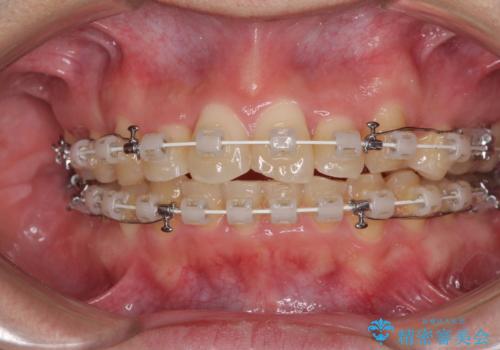

- 矯正装置

- 審美装置

咬合力が非常に強く、抜歯したスペースがなかなか閉じないであろうことは予想できましたが、思っていた以上に期間がかかりました。

前歯のすり減りも著しかったため、仕上げの位置の調整にも期間を要しました。